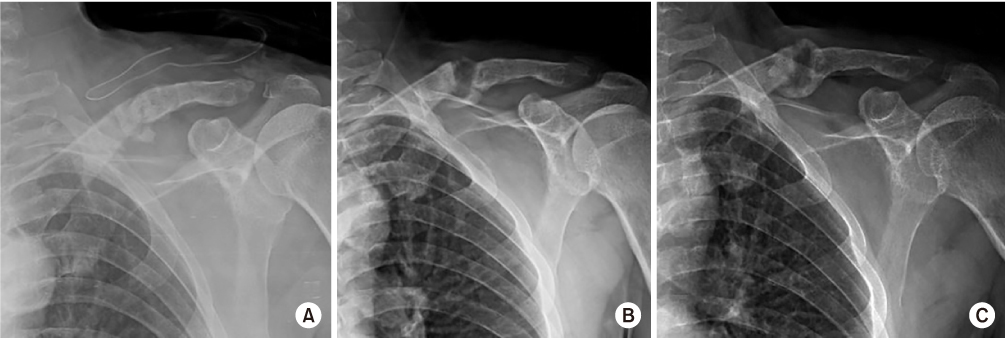

Postoperative neurovascular status was intact, and we found no abnormal findings until postoperative day 3. On postoperative day 4, the patient presented with numbness in the left hand and decreased strength. A grade 1/5 in thumb extension and flexion, wrist extension, and finger extension, flexion, and abduction was found in addition to a grade 3/5 in wrist flexion and elbow flexion and extension. A haematoma formation at the operation site was suspected because of the acute onset of symptoms on postoperative day 4. On postoperative day 5, an ultrasound was performed for evaluation of a possible haematoma, but no definite mass or haematoma was found around the clavicle. On postoperative day 6, diffusion magnetic resonance imaging (MRI) was performed to evaluate for possible acute stroke, but there was no evidence of acute infraction. Additionally, on postoperative day 6, cervical spine MRI was performed to evaluate the cervical spine. Cervical spine MRI demonstrated a fibrotic mass lesion around a small bony fragment inferior to the clavicle. This lesion was compressing the adjacent brachial plexus causing signal changes within the brachial plexus (Fig. 3). Based on the MRI findings, we removed the implant and made a superior angulation to decompress the brachial plexus. There was no haematoma intraoperatively, and we left grafted bone. We put a Velpeau sling on the patient's left shoulder after surgery (Fig. 4).

(A) Immediate postoperative radiograph after the second surgery. Callus bridging is seen on the 3-month follow-up radiograph (B) and consolidation processing on the 6-month follow-up radiograph (C).

On postoperative day 1, the patient presented with improved strength of thumb flexion and finger flexion to a grade 3/5 with decreased numbness of the left hand. On postoperative day 3, wrist extension improved to a grade 2/5 and left hand numbness was nearly resolved. Electromyography at 12 days postoperatively demonstrated diffuse brachial plexopathy, especially affecting the upper trunk. The patient underwent physical and exercise therapy until discharge. At the time of discharge, on postoperative day 30, thumb extension and finger extension and abduction were graded as 3/5, and all other left hand strengths were graded as 4/5. A Velpeau sling was not applied after discharge. On radiographs 3 and 6 months postoperatively, callus bridging and consolidation were visible (Fig. 4). On examination, there was no excess motion or tenderness at the fracture site, shoulder abduction and flexion were graded as 3/5 and 4/5, respectively, and all hand and elbow functions were fully recovered.